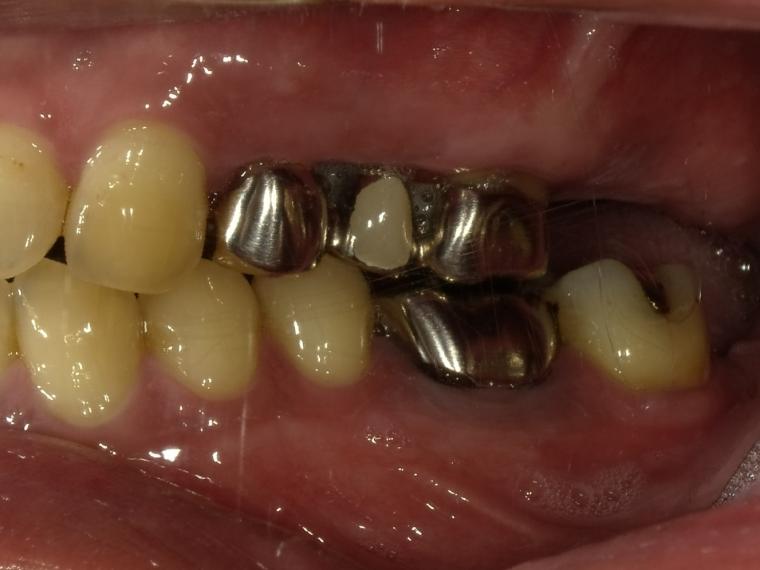

BEFORE

41歳男性/上5本欠損/インプラント埋込手術

上5本が虫歯になってしまった為治療をすることになった患者さんです。

虫歯が進行していて、歯を保存出来なかったため歯を抜いて人工の骨を足してからインプラントを

5本埋込した患者さんです。